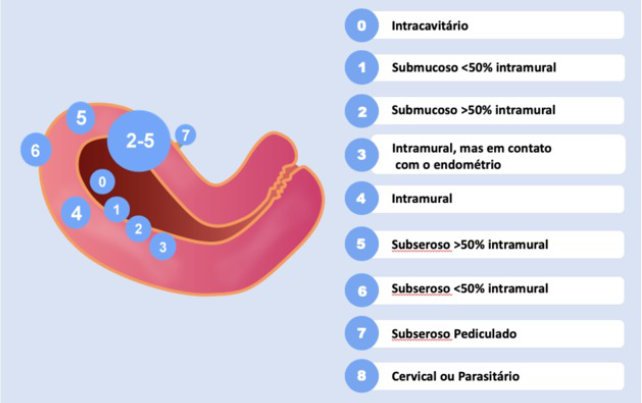

Os miomas podem ser classificados em: submucosos, intramurais e subserosos de acordo com a relação com endométrio (camada interna), miométrio (camada muscular e intermédia) e serosa(camada mais externa uterina).

A Federação Internacional de Ginecologistas e Obstetras (FIGO) desenvolveu uma classificação para ser utilizada nos exames de imagens e permitir ao médico assistente um melhor entendimento da relação dessas lesões com a cavidade uterina, com o miométrio e com a camada serosa que recobre o útero, auxiliando assim na tomada de decisões sobre o tratamento,